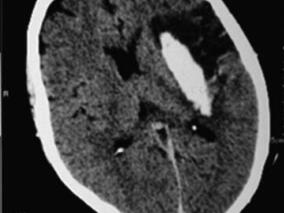

1小时条评论1 病例简介 患者男,65岁,因左侧口角流涎2个月余,左侧肢体无力12日于2008年12月5日以脑出血收入我院。 图4.7-1颅脑CT示右侧颞顶叶片状高密度出血影,周围可见指样低密度水肿影(箭头) 现病史:患者在起病前2个月(2008年9月14日)出现左侧口角歪斜、流涎,...